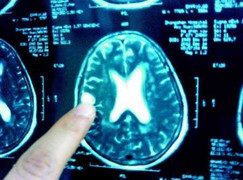

(VTC News) - Bệnh viện bệnh nhiệt đới trung ương vừa tiếp nhận một bệnh nhân bị ảnh hưởng thần kinh nghiêm trọng do nhiễm ấu trùng sán trong não.

Sau khi trải qua hàng loạt kiểm tra hóa nghiệm, bác sỹ phát hiện trong não có 2 khối di động trong não và chứa đầy sán.